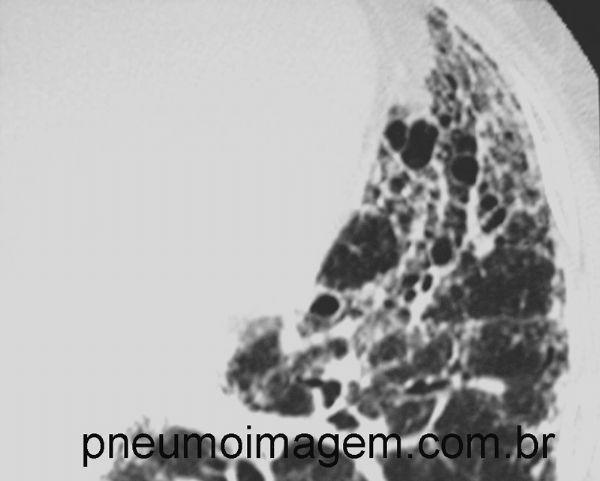

Detalhe de radiografia de tórax com pulmão em favo de mel.

Detail of chest X-ray with lung on honeycomb.

Alterações intersticiais pulmonares bilaterais difusas e com predomínio nas regiões subpleurais dos lobos inferiores, caracterizadas por espessamento septal interlobular, reticulado, bronquiolectasias de tração, bronquiectasias de tração e faveolamento. Esse é o padrão de pneumonia intersticial usual (PIU), característica da Fibrose Pulmonar idiopática (FPI).

Diffuse biliary interstitial changes with predominance in the subpleural regions of the lower lobes, characterized by interlobular septal thickening, traction bronchiolectasis, traction bronchiectasis and honeycombing. This is the pattern of usual interstitial pneumonia (UIP), characteristic of idiopathic pulmonary fibrosis (IPF).